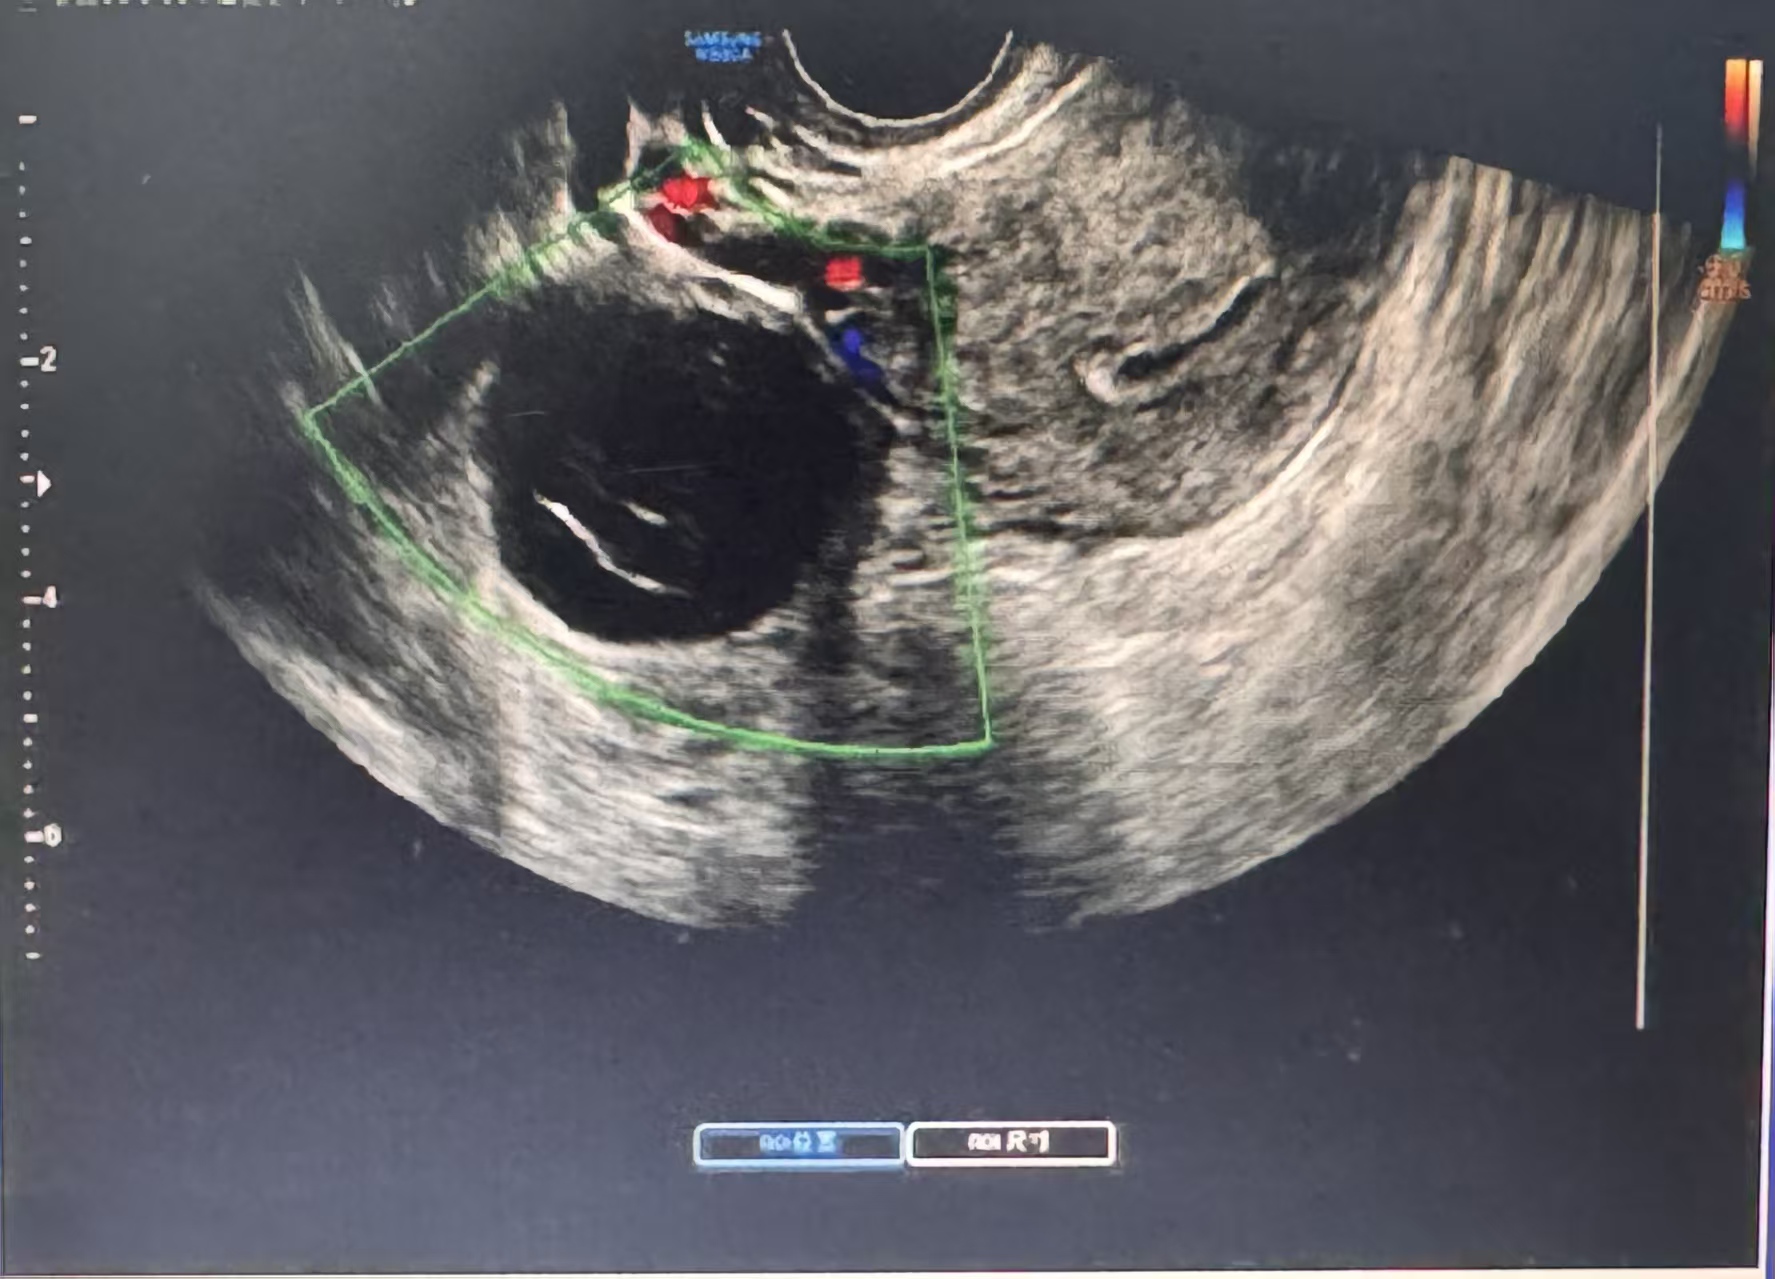

超声检查无辐射、无创、实时,能清晰显示囊肿的位置、大小、形态、内部结构和血流情况,宛如一位敏锐的侦探,为我们提供第一手证据。经阴道超声分辨率更高,是观察卵巢细节的利器。

清澈如泉(无回声):常为单纯性囊肿,良性可能性大。

细雨蒙蒙(稀疏点状回声):可能为出血性囊肿或巧克力囊肿(子宫内膜异位囊肿)。

3. 血流信号:通过彩色多普勒超声观察。良性囊肿通常血流信号稀少、规则。若实性部分或分隔上探及丰富、紊乱的血流信号,则提示生长活跃,需高度重视。